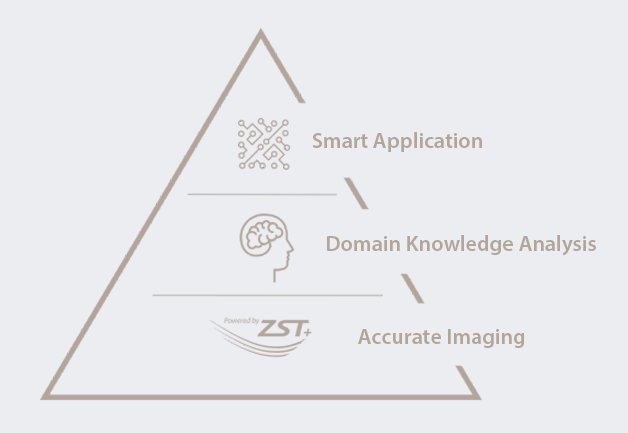

Avec l'Êvolution de la sociÊtÊ et les prÊoccupations croissantes concernant la santÊ des femmes, de plus en plus de femmes sont conscientes de l'importance des Êchographies rÊgulières en gynÊcologie obstÊtrique. La demande croissante d'examens Êchographiques a sans aucun doute lancÊ un nouveau dÊfi aux Êchographistes, sans compter que la demande est de plus en plus segmentÊe. Pour simplifier le processus et permettre à davantage de femmes de bÊnÊficier de services de diagnostic par Êchographie de grande qualitÊ, Mindray s'engage à innover et propose une gamme complète de solutions intelligentes pour les soins de santÊ des femmes et des enfants, gr?ce à Zone Intelligence?. Nous espÊrons doter les Êchographistes d'une ??arme magique?? leur permettant de rÊpondre à de nombreux scÊnarios d'examen, avant la grossesse, en cours de grossesse, pendant le rÊtablissement post-partum et chez le nouveau-nÊ, pour protÊger davantage leur santÊ.

Une gamme complète de solutions intelligentes pour les soins de santÊ des femmes et des enfants gr?ce à Zone Intelligence?